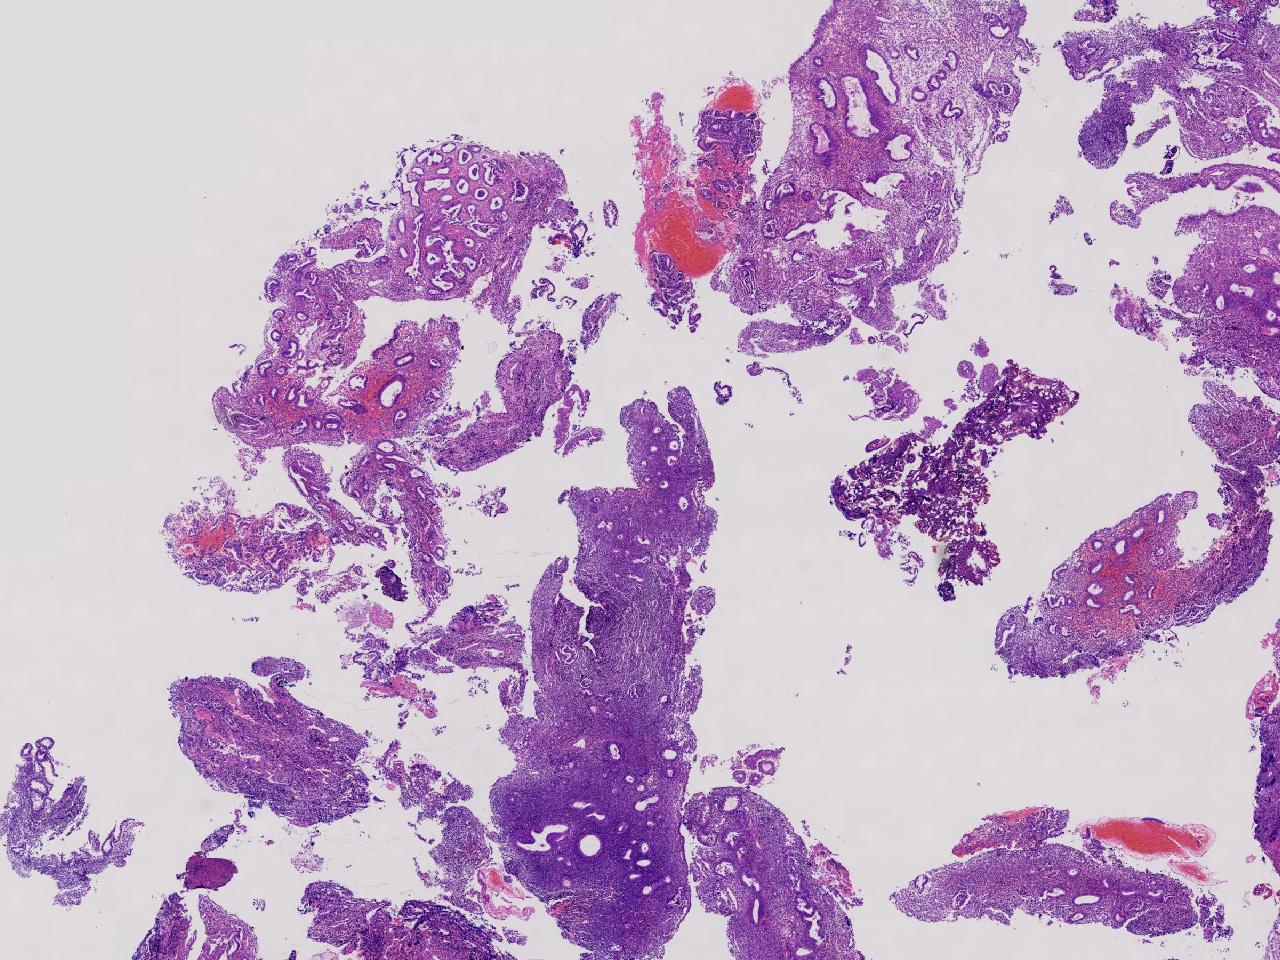

性别

女

年龄

55岁

女,55岁,月经紊乱4年,彩超示:子宫内膜增厚(内膜厚15.7mm),末次月经:2025年7月27日。

宫腔镜下子宫内膜活检

灰粉色不整形软组织多块,1.5X0.8X0.6厘米。

考虑:子宫内膜增生伴子宫内膜炎

子宫内膜增生紊乱,内膜息肉样结构